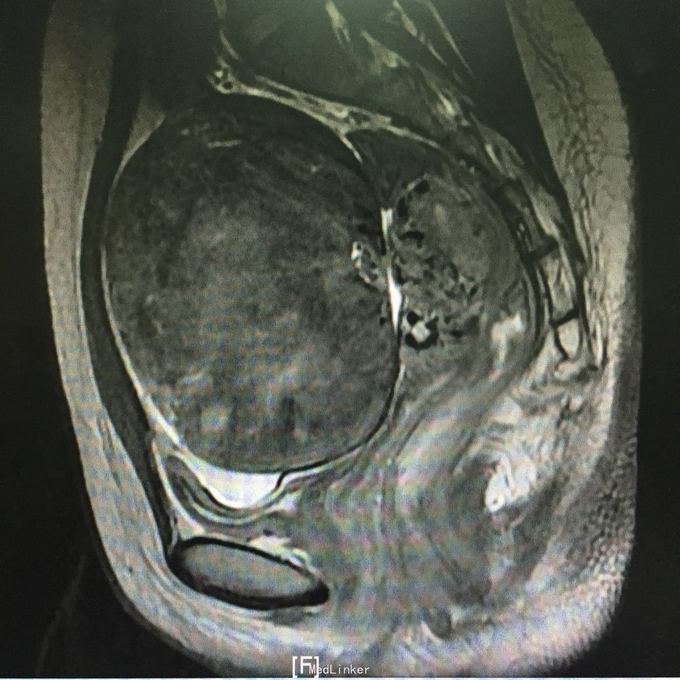

查体:子宫前位,增大如孕12周,可触及一直径约10cm包块,实性,表明光滑,似与子宫相连,活动度科,无压痛。入院后查肿瘤标志物未见异常。彩超是:子宫右前方见一个类圆形低回声团,按压似与子宫右相对运动,大小108*105mm,边界清,内部回声不均匀,见栅栏样衰减。盆腔MR示:子宫前方巨大占位,考虑间叶源性肿瘤与浆膜下子宫肌瘤鉴别。

入院诊断:盆腔包块查因。术中见,子宫前位,正常大小,子宫前壁浆膜下肌瘤,大小约10*10cm,表明光滑,蒂部宽约3cm,近宫底,子宫质地软,活动好,双附件未见异常,予以行子宫肌瘤剔除术,术中冰冻示:子宫平滑肌瘤,部分间质水肿。